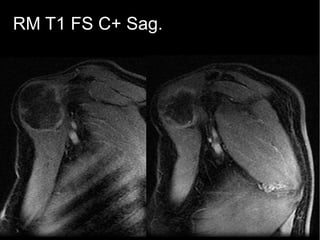

RM T1FS C+:

Realce anular periférico y

de algunos septos internos.

Área central hipointensa,

correspondencia con polo

hiperintenso T2.

Vascularización satélite.

RM T1 FS C+ Sag.

RM T1 FSC+ Sag.

RM T1FS C+: Tendenciaa realce progresivo en fase tardía con zonas de lavado.